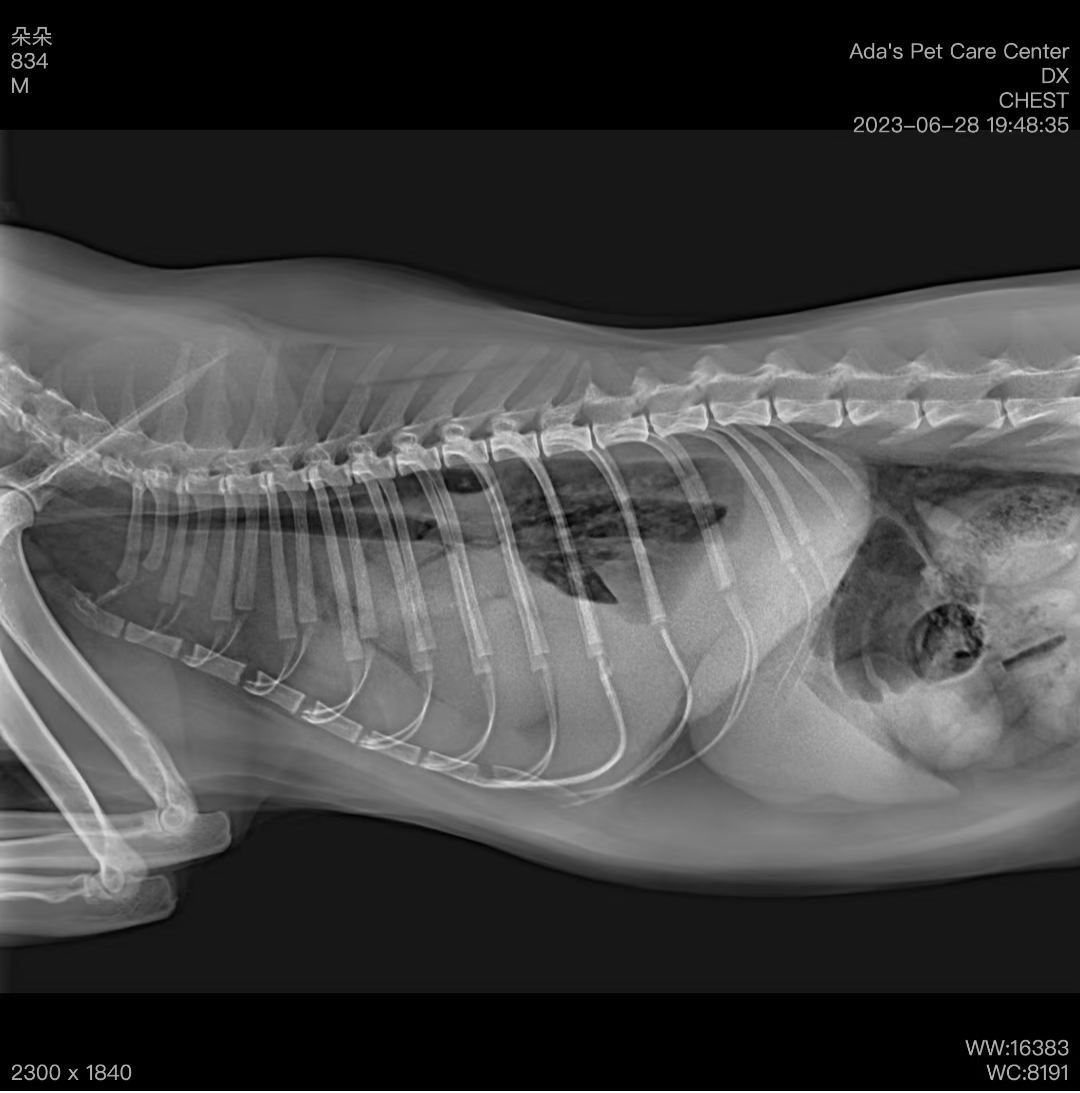

猫咪刚到医院时反应很差,呼吸困难,舌头发紫。吸氧后,呼吸情况稍微缓解。拍了胸部X光,结果显示胸腔里有明显的积液。我们做了胸腔穿刺,抽出了200ml乳黄色的积液,化验后确定是乳糜胸。